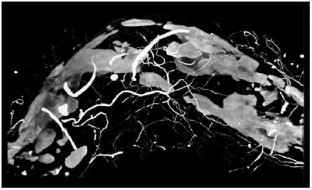

Feinstein SB (2006) Contrast ultrasound imaging of the carotid artery vasa vasorum and atherosclerotic plaque neovascularization. J Am Coll Cardiol 48: 236–243

Carlier S et al. (2005) Vasa vasorum imaging: a new window to the clinical detection of vulnerable atherosclerotic plaques. Curr Atheroscler Rep 7: 164–169